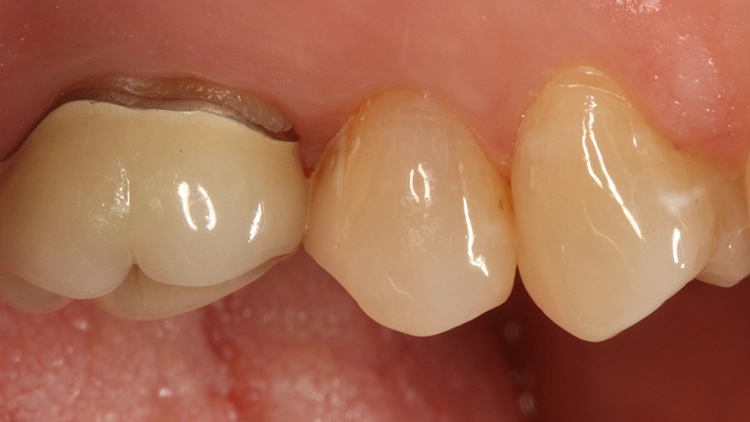

Die Patientin bat damals um einen Austausch des Goldinlays, da ihr keine Möglichkeiten einer Nacharbeitung am Inlayrand angeboten werden konnten. Die Inlayversorgung zeigte sich sehr weit in den Approximalraum ausgedehnt (Abb. 11 und 12), was nach Aussage der Patientin an der damaligen Indikation eines Lückenschlusses zwischen den Zähnen 25 und 26 lag.

Nach Entfernung des Goldinlays zeigte sich eine kariesfreie Kavität, die lediglich nachfiniert werden musste. Im Zuge dieses Arbeitsschrittes wurde auch die Klebefläche angefrischt. Aufgrund der vorangegangenen Federrandpräparation ergab sich eine für eine Keramikversorgung (die als Alternative diskutiert worden war) sehr ungünstige Gestaltung des approximalen Kastens.